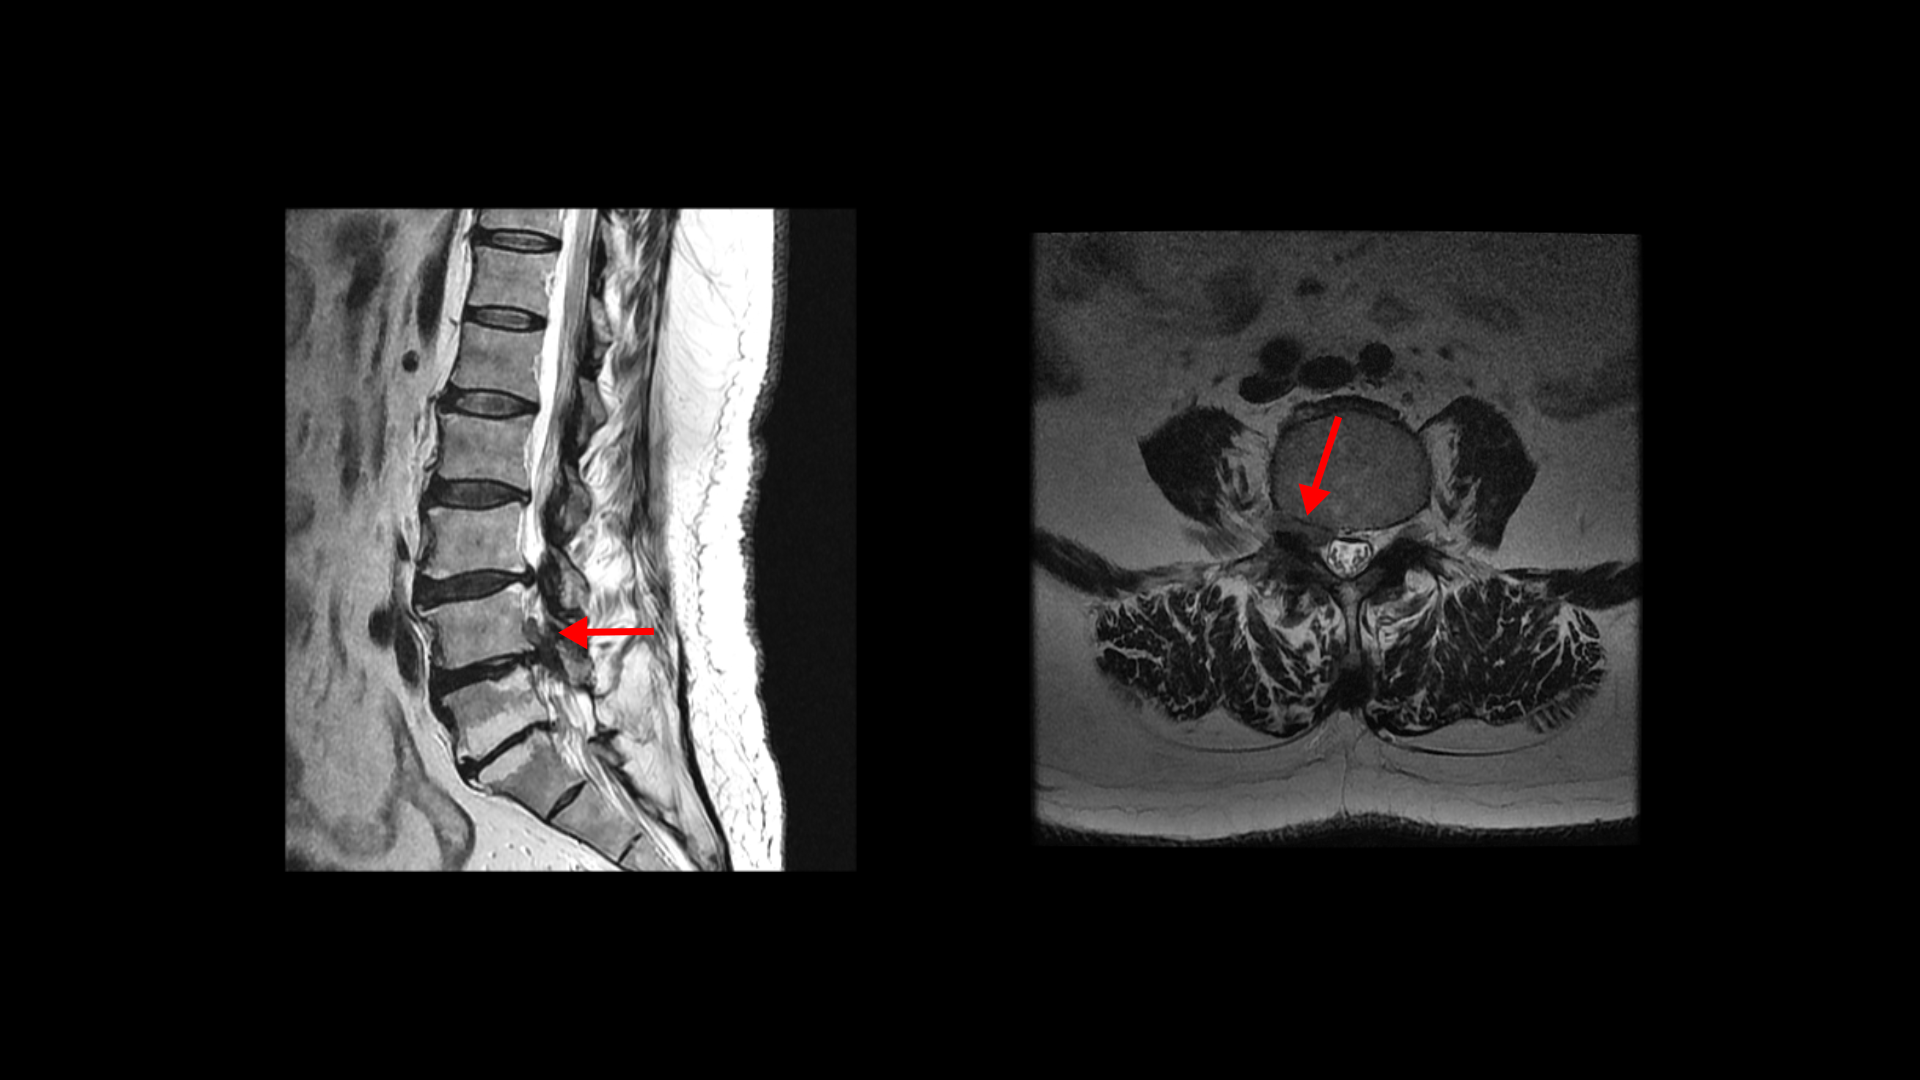

5번 1번을 보면 후궁에 수술한 자국이 보입니다.

4번 5번에도 후궁 쪽 양쪽으로 수술한 자국이 보입니다.

올해 초에 디스크가 4번 5번에서 또 오른쪽으로 심하게 터져서 결국은 후궁과 후관절, 황색인대를 모두 다 제거하고 나사를 박는 유합술을 하셨습니다.